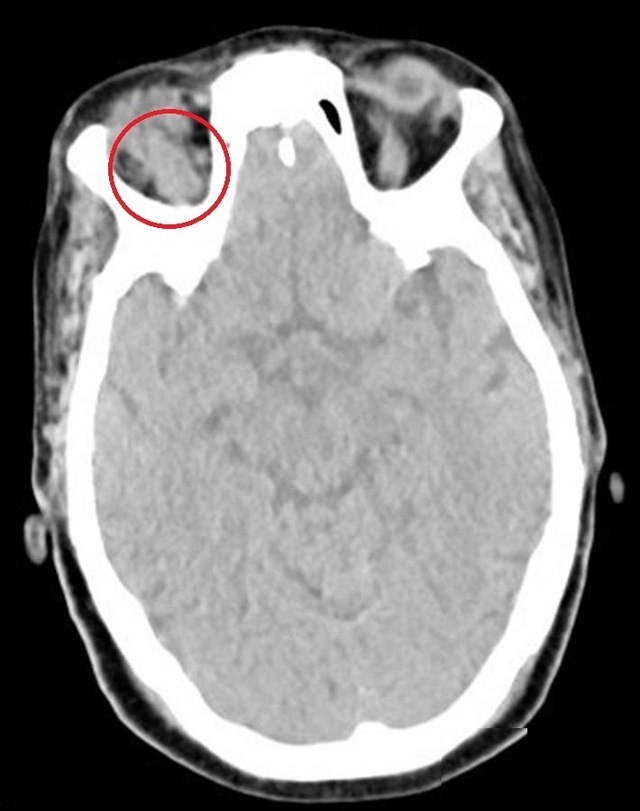

图 4 为平扫 CT,可见上直肌明显增粗(箭头)